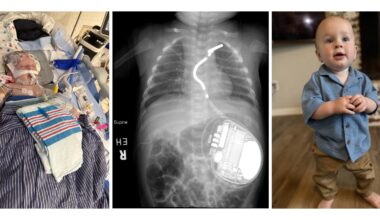

Speed, Expertise and Advanced Technology Combine to Save an Infant’s Heart

Meet Fletcher St. Jean, the youngest child to receive an EV-ICD device to manage idiopathic ventricular fibrillation CINCINNATI,…